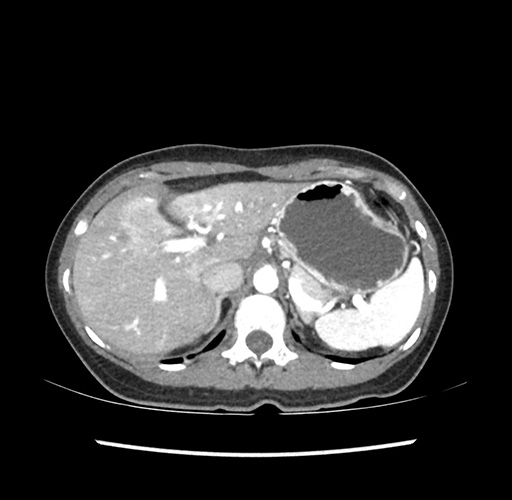

Imaging Analysis

Look through the patient's CT scan to identify any areas of concern for the necessary procedure.

Based on your CT findings, which issue(s) would give reason for "planned slowing down moment(s)" in this case?

Considering a standard left lateral sectionectomy procedure, what step(s) of the operation would you do differently in this case ?